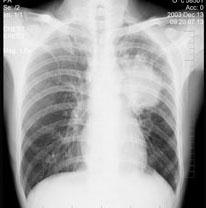

问题 女性,51岁,胸痛数月,痰血两天,X线检查见图,最可能的诊断是 ( )

选项 A、左肺转移瘤 B、支气管扩张 C、左侧炎性假瘤 D、左侧纵隔肿瘤 E、左肺癌

答案 E